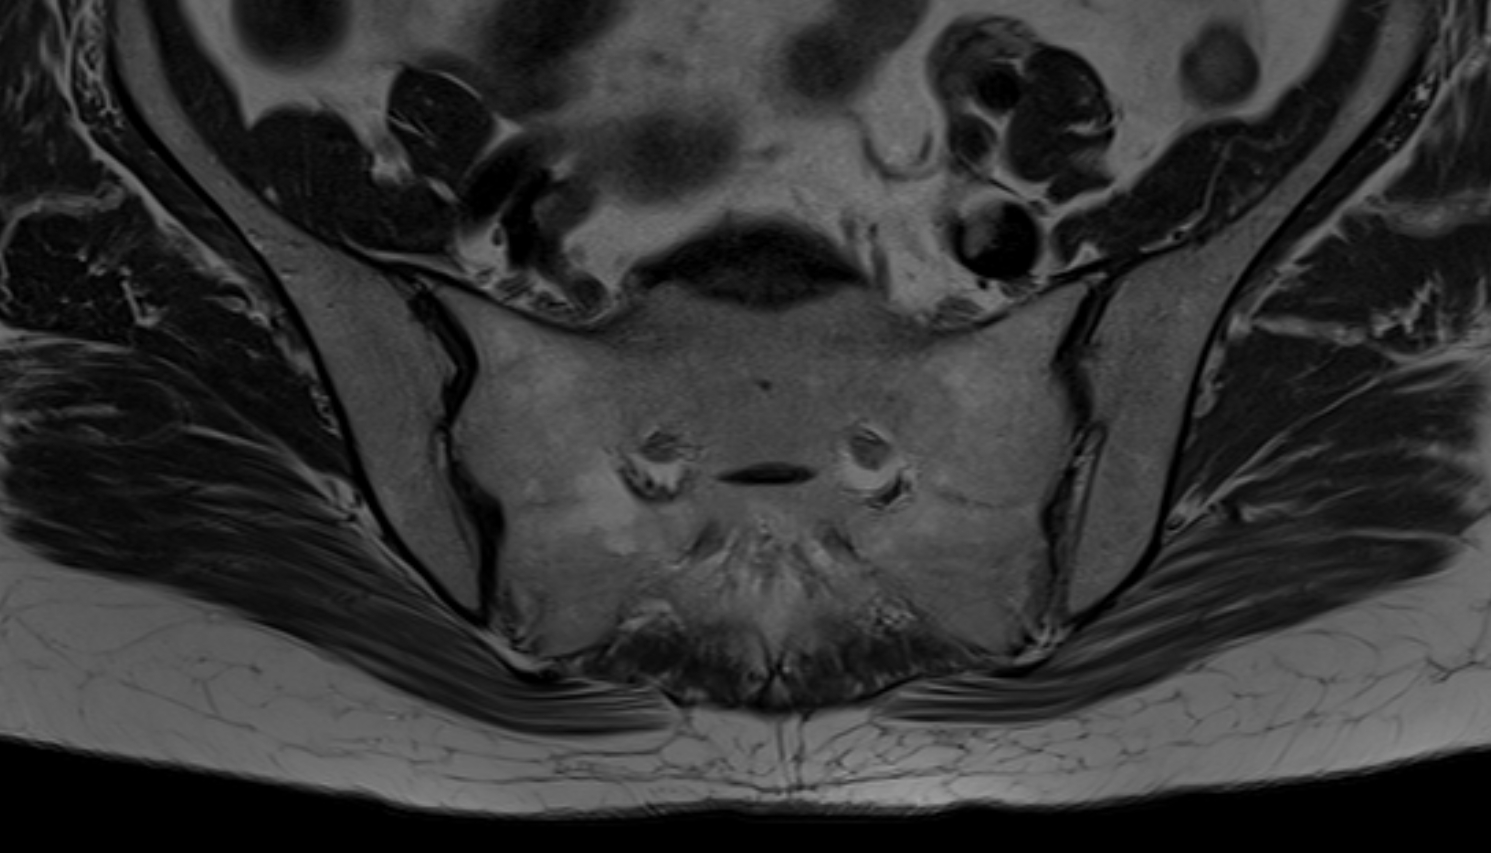

- Uterus

- Body of uterus

- Fundus of uterus

- Cervix of uterus

- Isthmus of uterus

- Vagina

- Ovaries

- Right ovary

- Left ovary

- Pubic symphysis